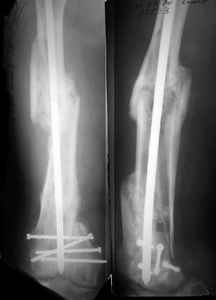

I presented a series of ~25 such cases at EuroTrauma'2004. Many cases were discussed here. I attach am example. Look also recent cases at http://www.hwbf.org/hwb/conf/alex58/scfx.htm,

http://www.hwbf.org/hwb/conf/alex63/alex63.htm

KEMMD> B. Fixation loosening: distal cutting of the nail, non-unions do happen

KEMMD> (cases attached).

The nail can be unlocked in the proximal fragment to prevent it.